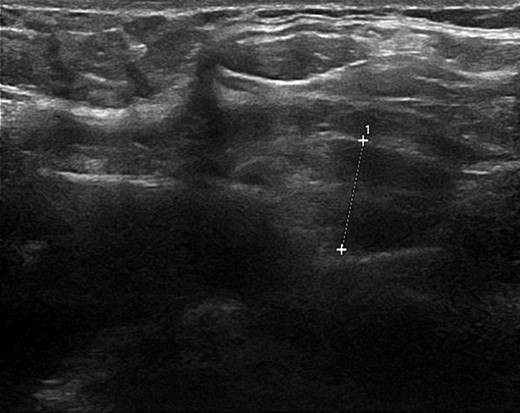

From these results PHPT was suspected and the hypercalcaemia treated with intravenous fluids and a pamidronate infusion. Calcium levels normalized over the next few days along with her psychiatric symptoms suggesting a causative relationship. An ultrasound neck revealed an 11 mm lesion with echogenicity and internal vascularity, likely to be an atypical parathyroid adenoma (Fig. 1). A Sestamibi scintigraphy scan was inconclusive in correlating with the ultrasound or clinical impression, however, evidence was sufficient to warrant surgical exploration with removal of the adenoma as a definitive treatment for the PHPT and psychosis.

Ultrasound neck image illustrating the parathyroid adenoma measuring 11 mm with echogenicity and internal vasculature.